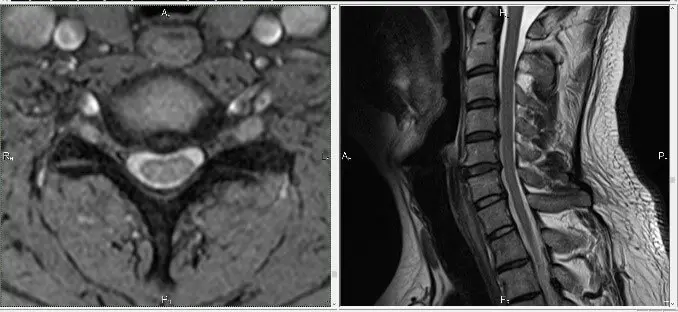

При тривалих і стійких больових проявах з боку хребта, крім МРТ шиї, іноді необхідно робити МРТ-обстеження грудного відділу.

Це необхідно для диференціальної діагностики. Наприклад, ураження грудного відділу хребта метастазом також може викликати біль у шиї: